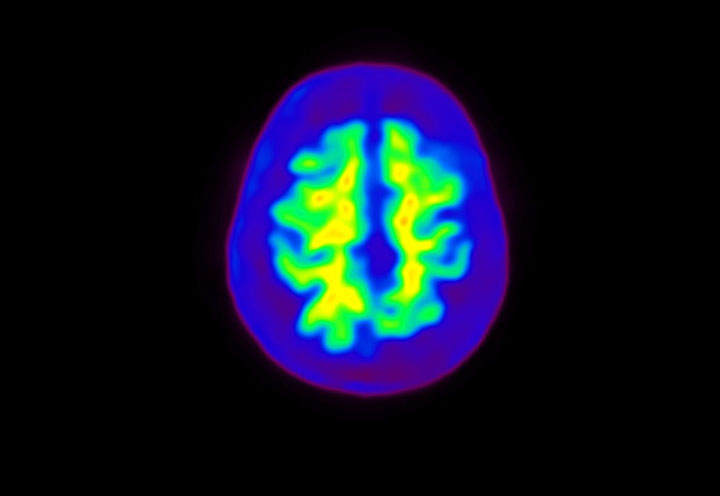

Head / Case4 : Amyloid

Axial

Courtesy : Kindai University Hospital

- Imaging protocol

- Injected dose: 3.21 MBq/kg, 18F-Flutemetamol

- Uptake time: 100 minutes

- Scan time: 20 minutes